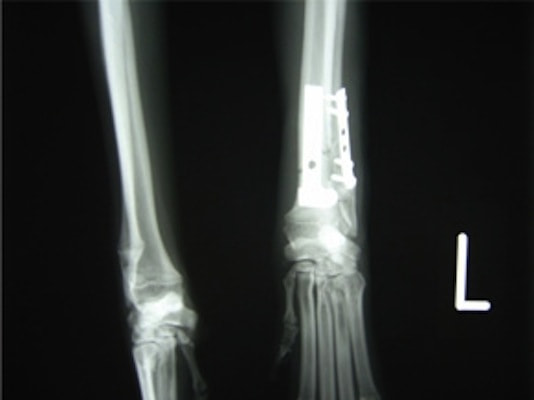

トイプードル 右遠位橈尺骨短斜骨折のALPSによる内固定

Locking Compression Plate

LCPは、スクリュー(ネジ)とプレート(金属の板)をロックする特殊な構造により骨折部位を固定する新しい世代のプレートシステムです。ひとつのホールでロッキングスクリューとスタンダードスクリューの使用を選択できるユニークな構造をしているため、骨折断端間の圧迫を目的とした従来型プレート固定法に加え、高い角度安定性を有するロッキングスクリューを用いた固定法の選択が可能です。従来のプレートシステムでは困難だった部分の骨折や癒合不全の症例に高い治療効果をもたらします。